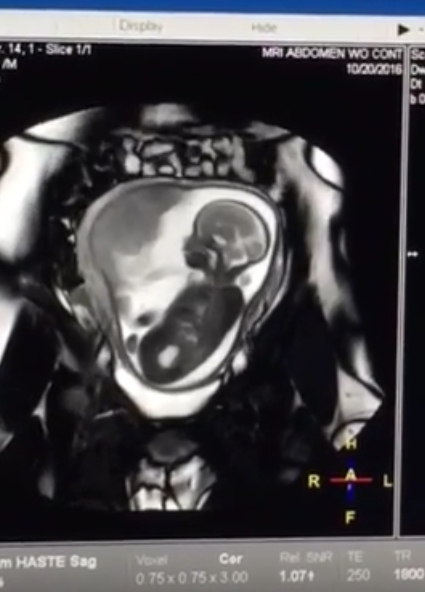

On to happier stuff! My wife has blogged about this (here, here, and here); the bottom line is that we’re expecting a baby boy on or around February 5th.

For me, the best part was after the MRI … when the radiology technician showed me some of the images and even a video…. I was astounded to see my favorite little alien moving around in there — it looked like he was having quite the dance party! It put a huge smile on my face the rest of the day to have a mental image of what was going on down below every time my stomach turns and tickles.